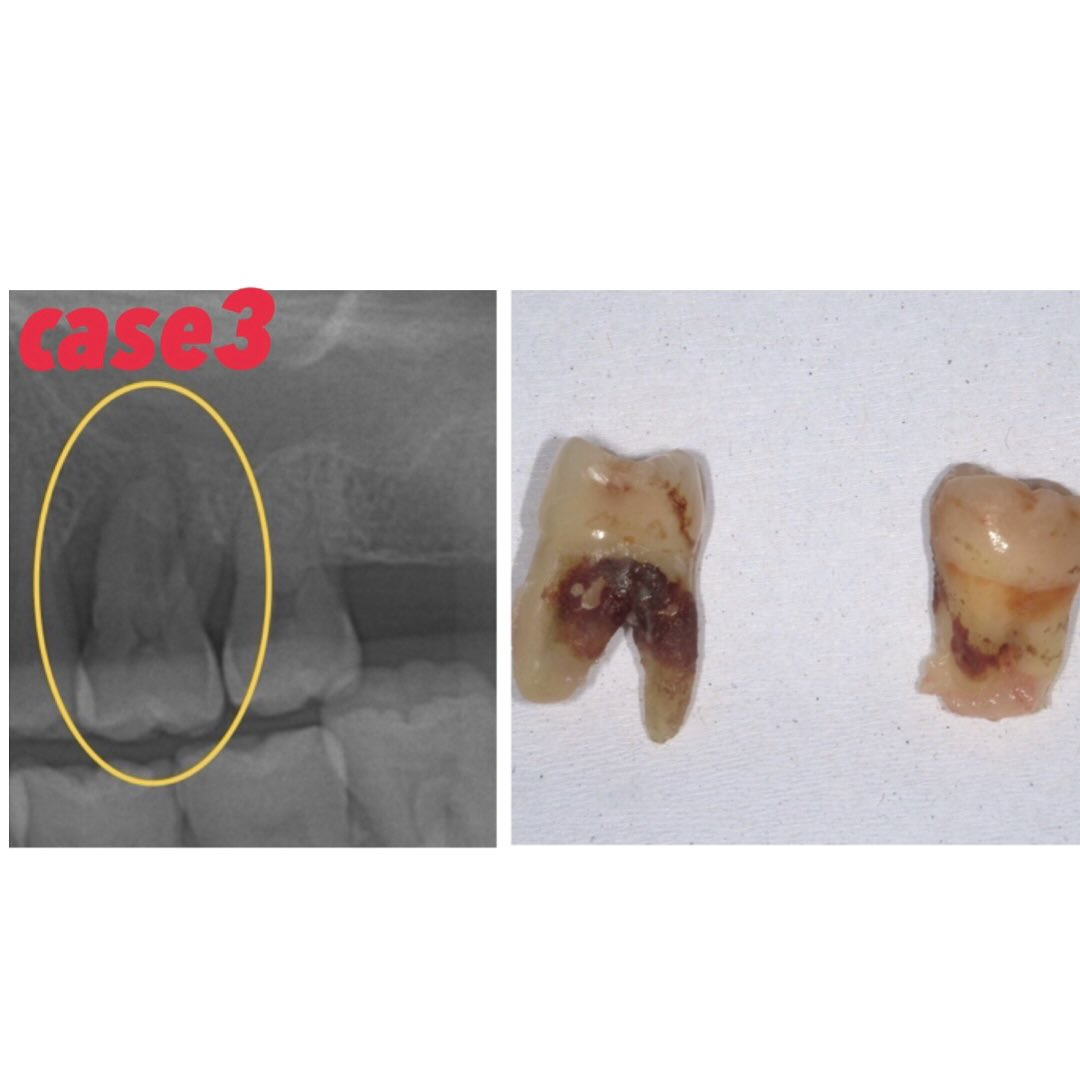

Case3の写真

2の方と同じく歯周病により抜歯した方のレントゲンと抜去歯です

根元に縁下歯石が付着しているのが分かります

Case2の方同様、歯を支える骨の吸収、歯の動揺も強かった為抜歯適応となりました